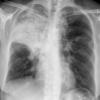

Case 3 RM & UL pneum PA

Date: 07/04/2004

Views: 5437